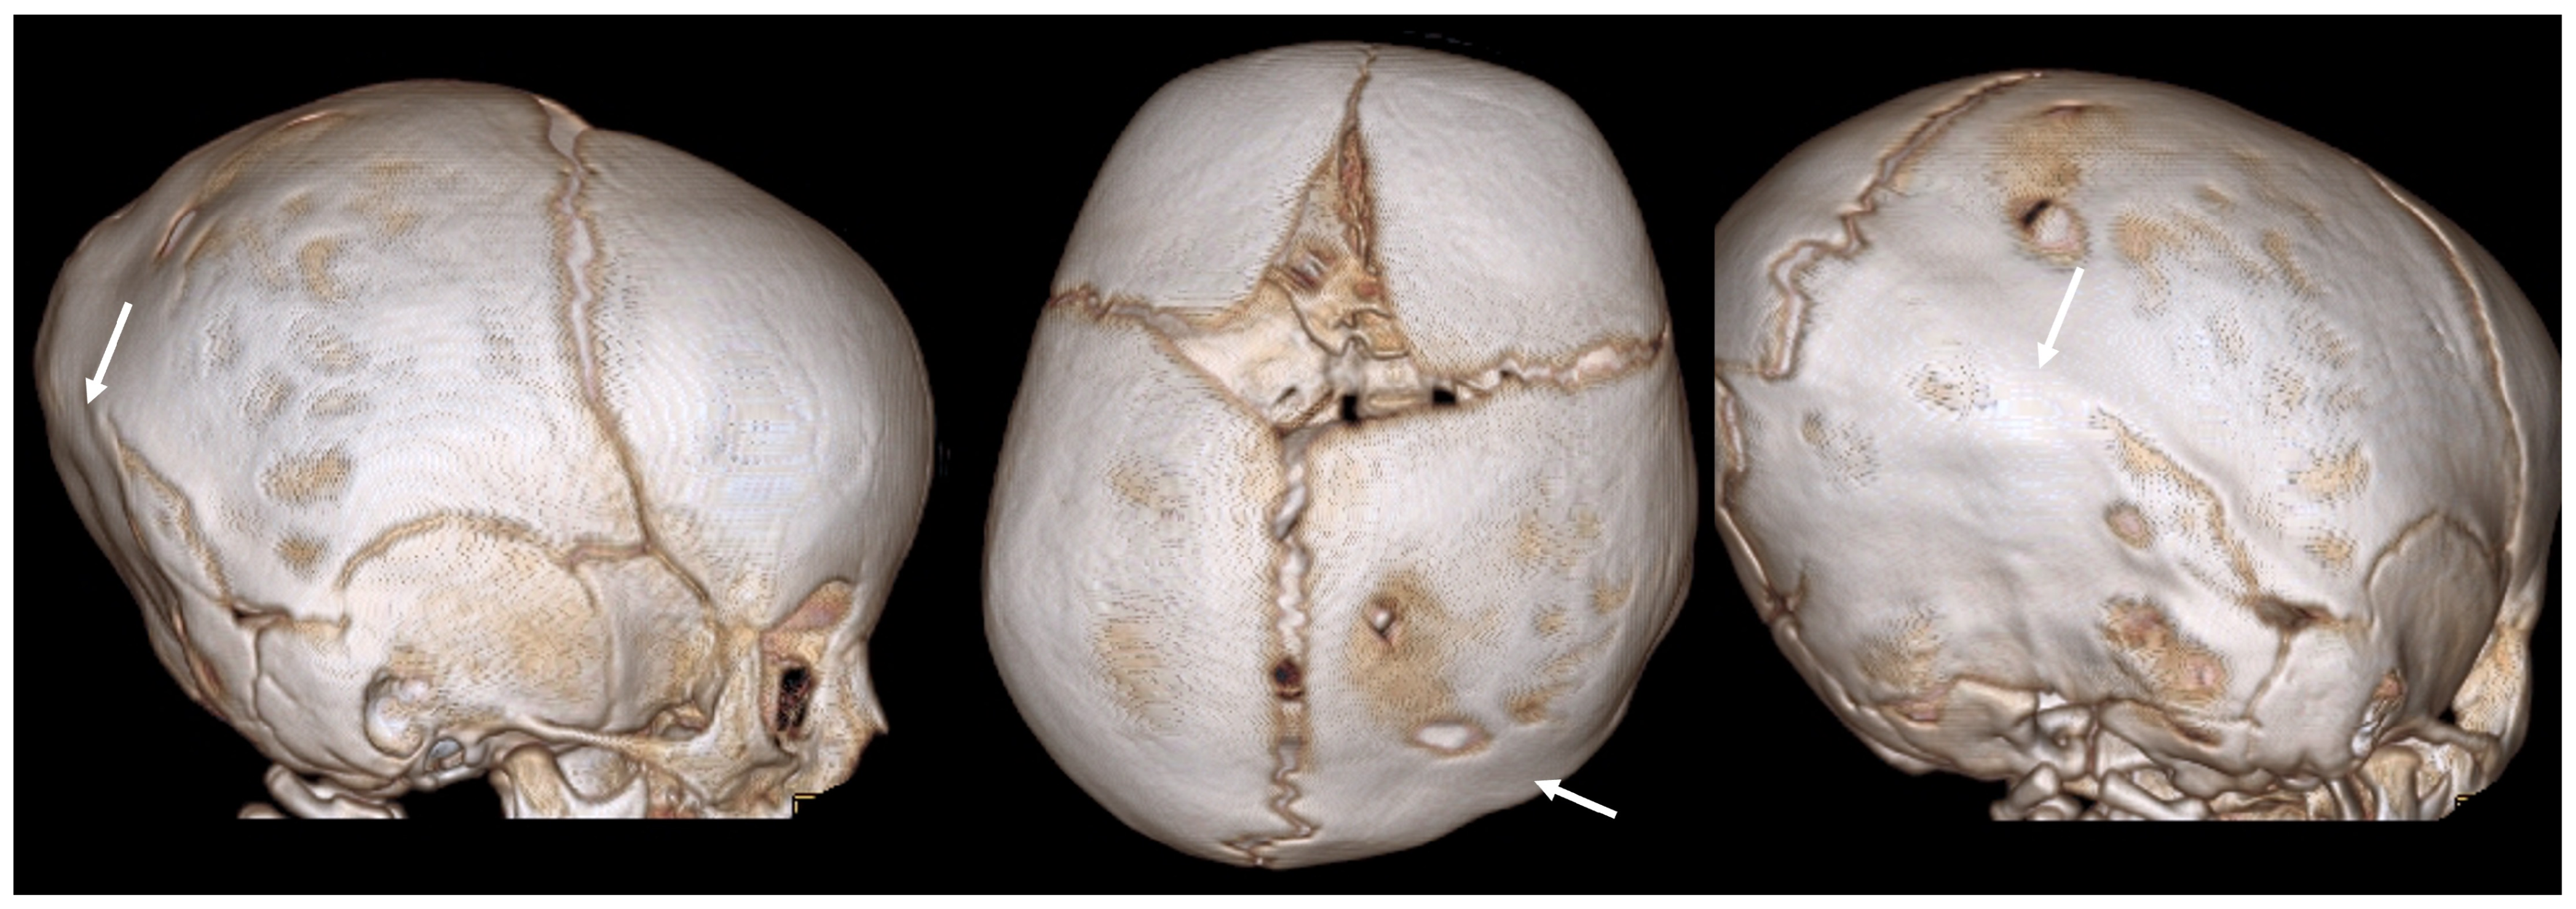

3.1. Ultrasound

3.2. Computed Tomography

- Proisy, M.; Riffaud, L.; Chouklati, K.; Tréguier, C.; Bruneau, B. Ultrasonography for the diagnosis of craniosynostosis. Eur. J. Radiol. 2017, 90, 250–255. [Google Scholar] [CrossRef]

- Soboleski, D.; Mussari, B.; McCloskey, D.; Sauerbrei, E.; Espinosa, F.; Fletcher, A. High-resolution sonography of the abnormal cranial suture. Pediatr. Radiol. 1998, 28, 79–82. [Google Scholar] [CrossRef] [PubMed]

- Whittall, I.; Lambert, W.A.; Moote, D.J.; Bookland, M.J.; Martin, J.E.; Hughes, C.D.; Hersh, D.S. Postnatal diagnosis of single-suture craniosynostosis with cranial ultrasound: A systematic review. Child’s Nerv. Syst. 2021, 37, 3705–3714. [Google Scholar] [CrossRef]

- Massimi, L.; Bianchi, F.; Frassanito, P.; Calandrelli, R.; Tamburrini, G.; Caldarelli, M. Imaging in craniosynostosis: When and what? Child’s Nerv. Syst. 2019, 35, 2055–2069. [Google Scholar] [CrossRef] [PubMed]